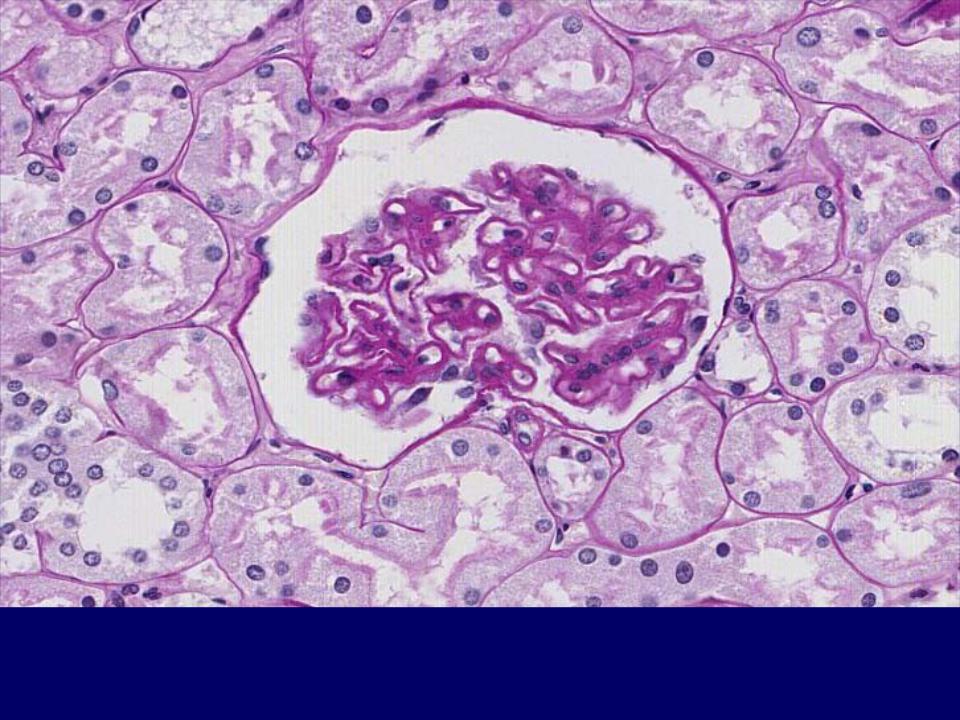

Симптомы подострого гломерулонефрита: фото и описание

Раздел: Визуальный дайджест